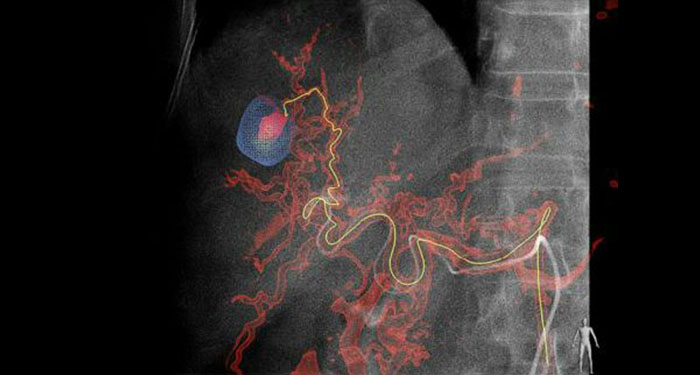

Equipos de radiología intervencionista